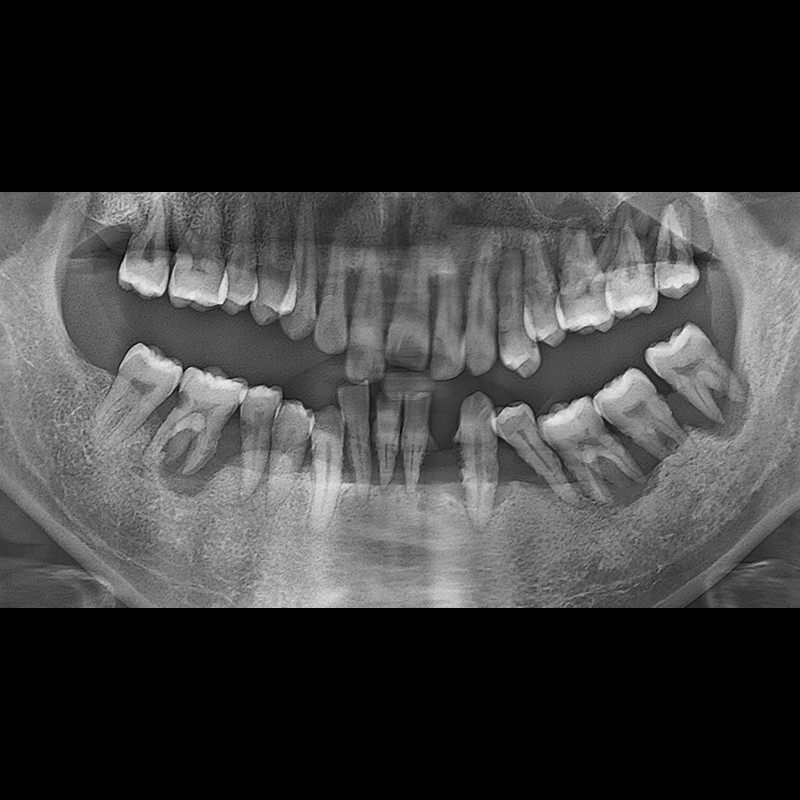

BEFORE AFTER

种植牙前后的照片 2025.05.30

在缺失的牙齿部分和难以挽救的牙齿位置植入了种植牙。